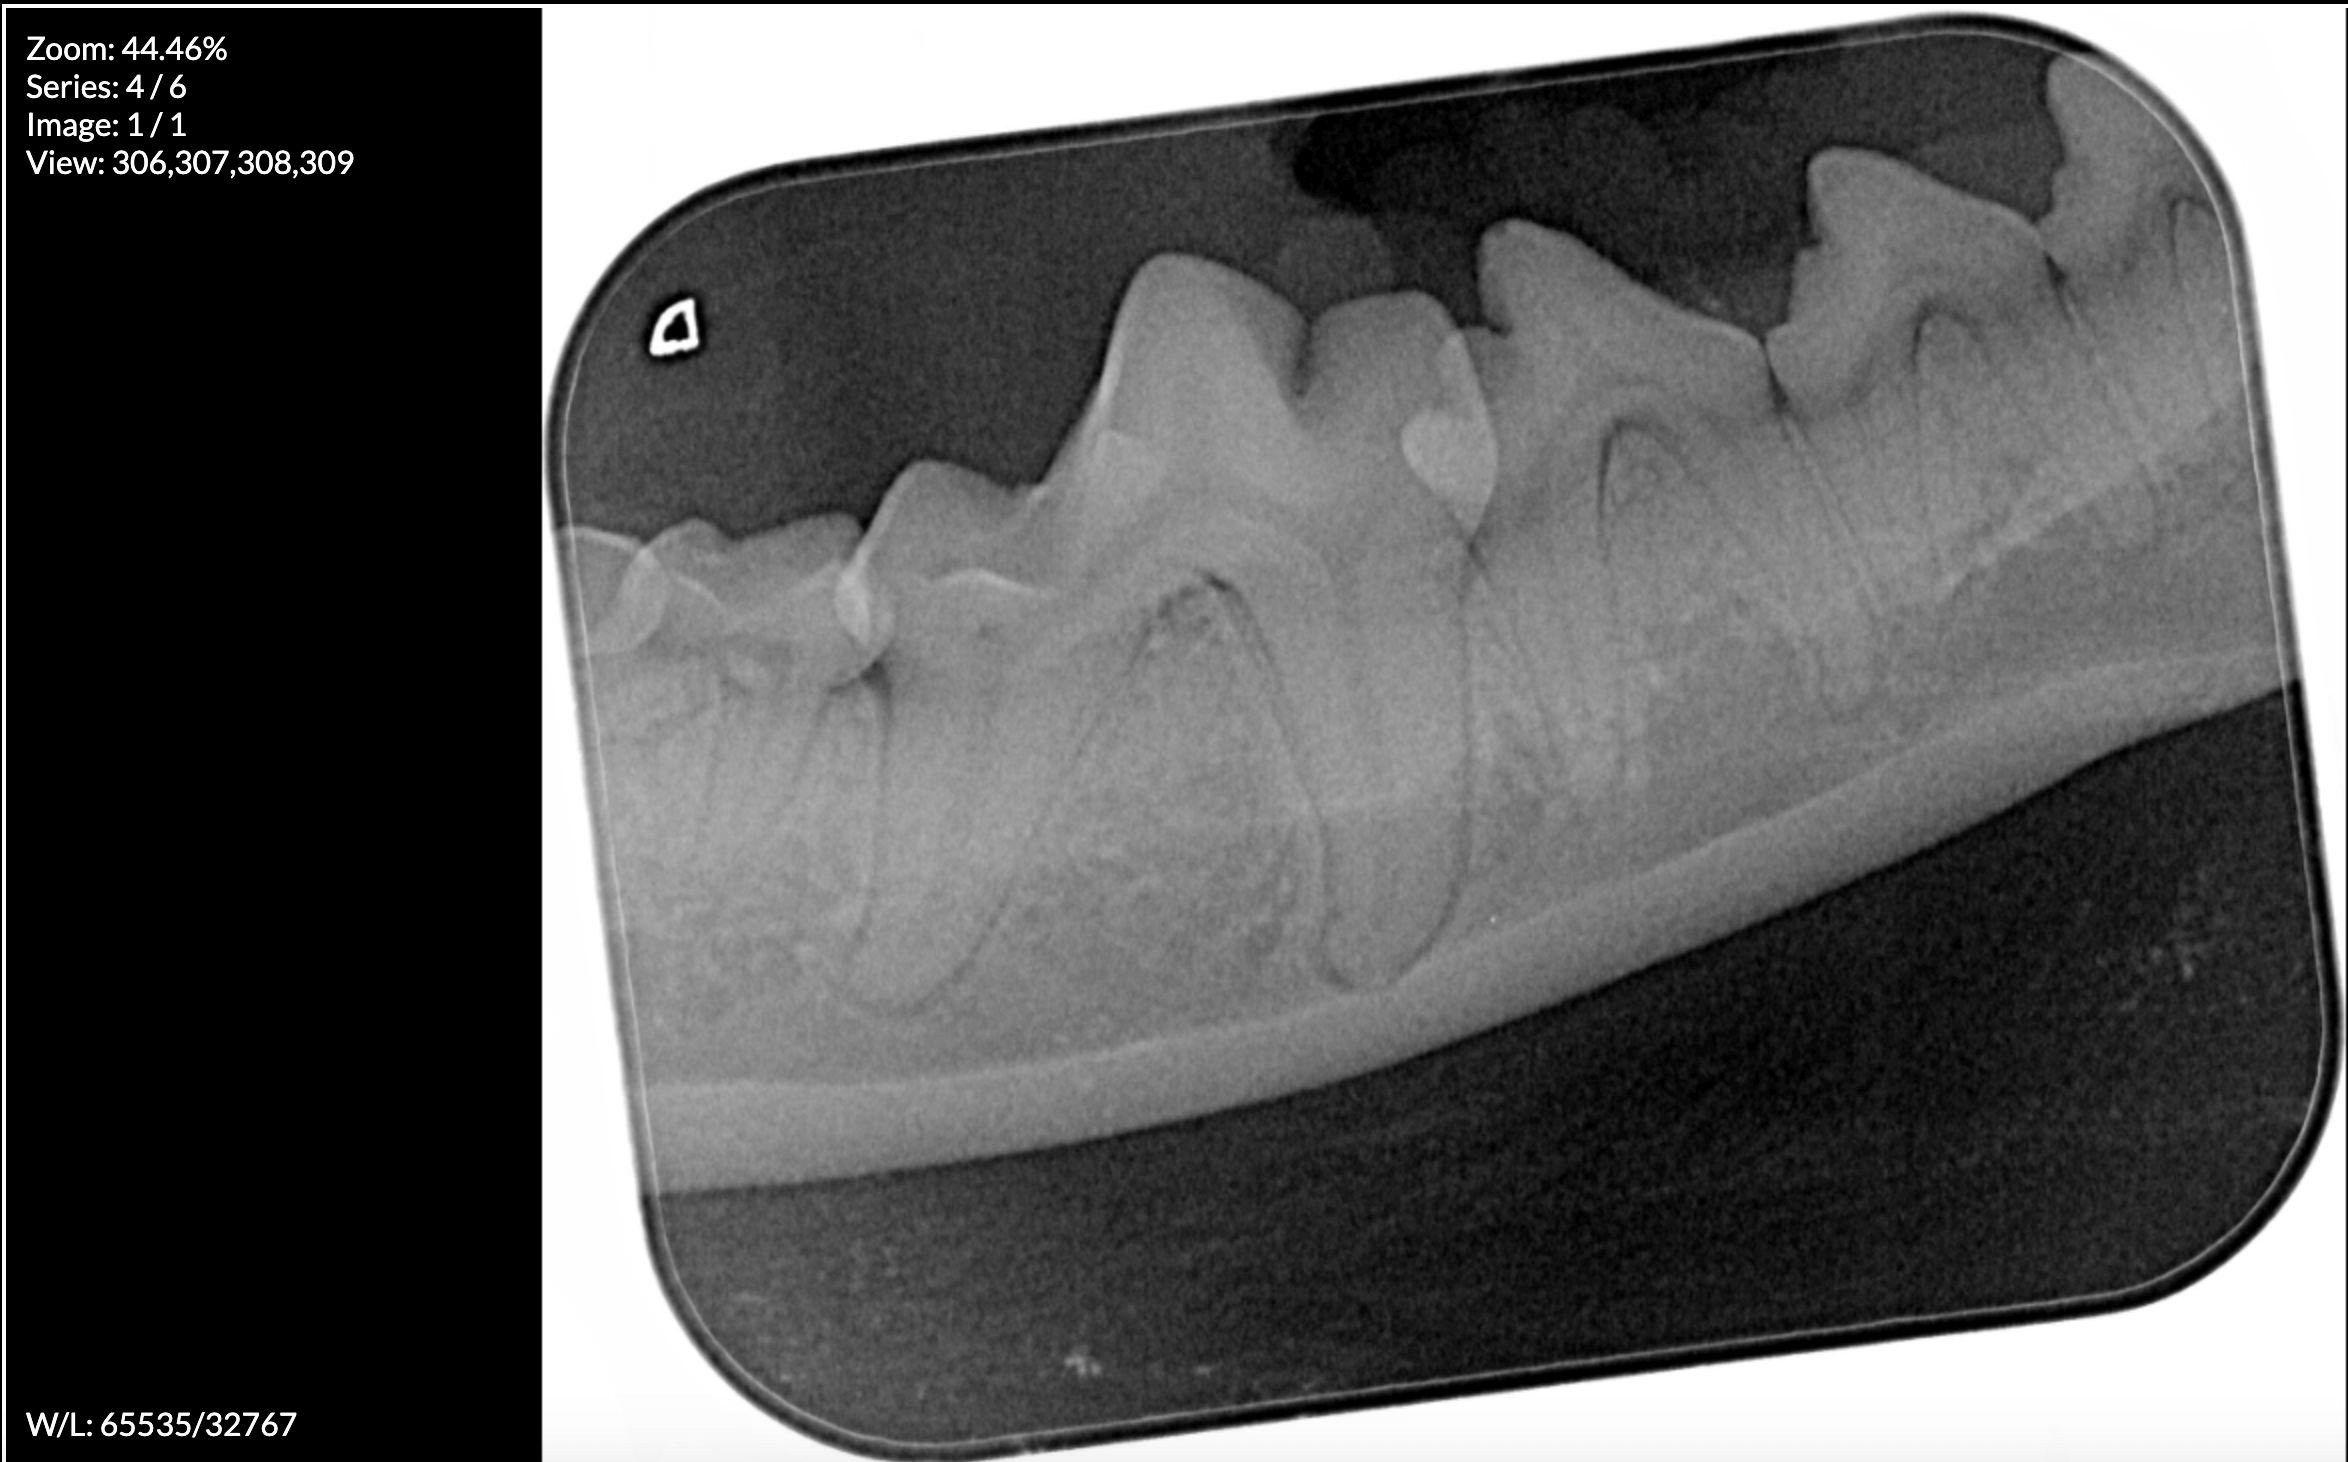

The Floreat Vet is fully equipped to carry out dental surgery on site. With our full suite of IM3 dental equipment, including the atraumatic VetTome and a state of the art Dental XRay machine, we prioritise the safety and comfort of your cat or dog while addressing their dental concerns.